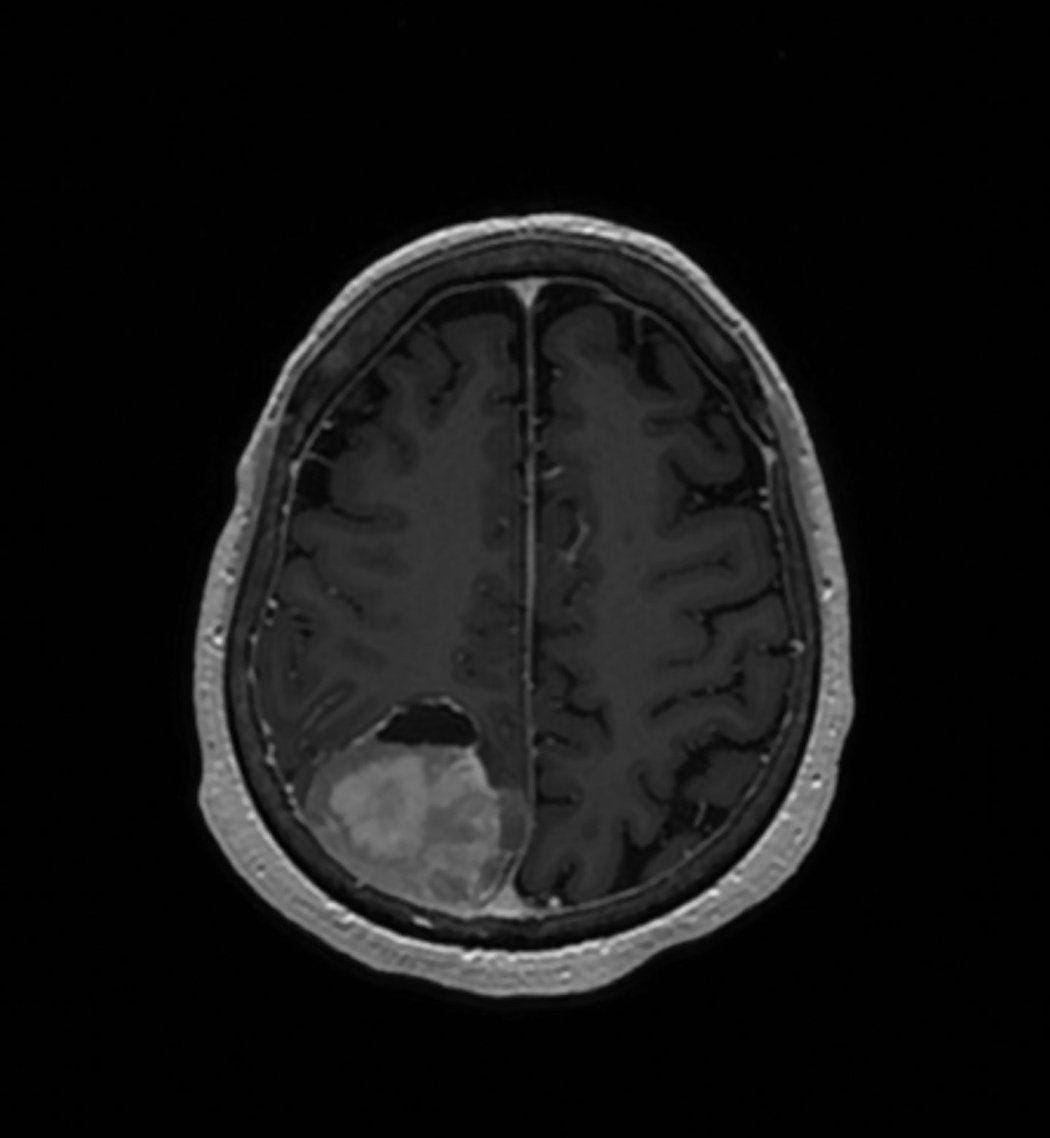

Depo-Provera (Brain Tumor Claims)

Depo-Provera is an injectable contraceptive. Lawsuits allege that prolonged use of the drug is associated with the development of meningiomas, a type of brain tumor that can cause serious neurological symptoms. Plaintiffs claim that the risks were not adequately disclosed. This litigation has expanded quickly and is now centralized in federal court. With thousands of claims already filed, the case is moving at a faster pace than many traditional pharmaceutical mass torts, and early trial settings are anticipated, making it one of the most closely watched emerging dockets.